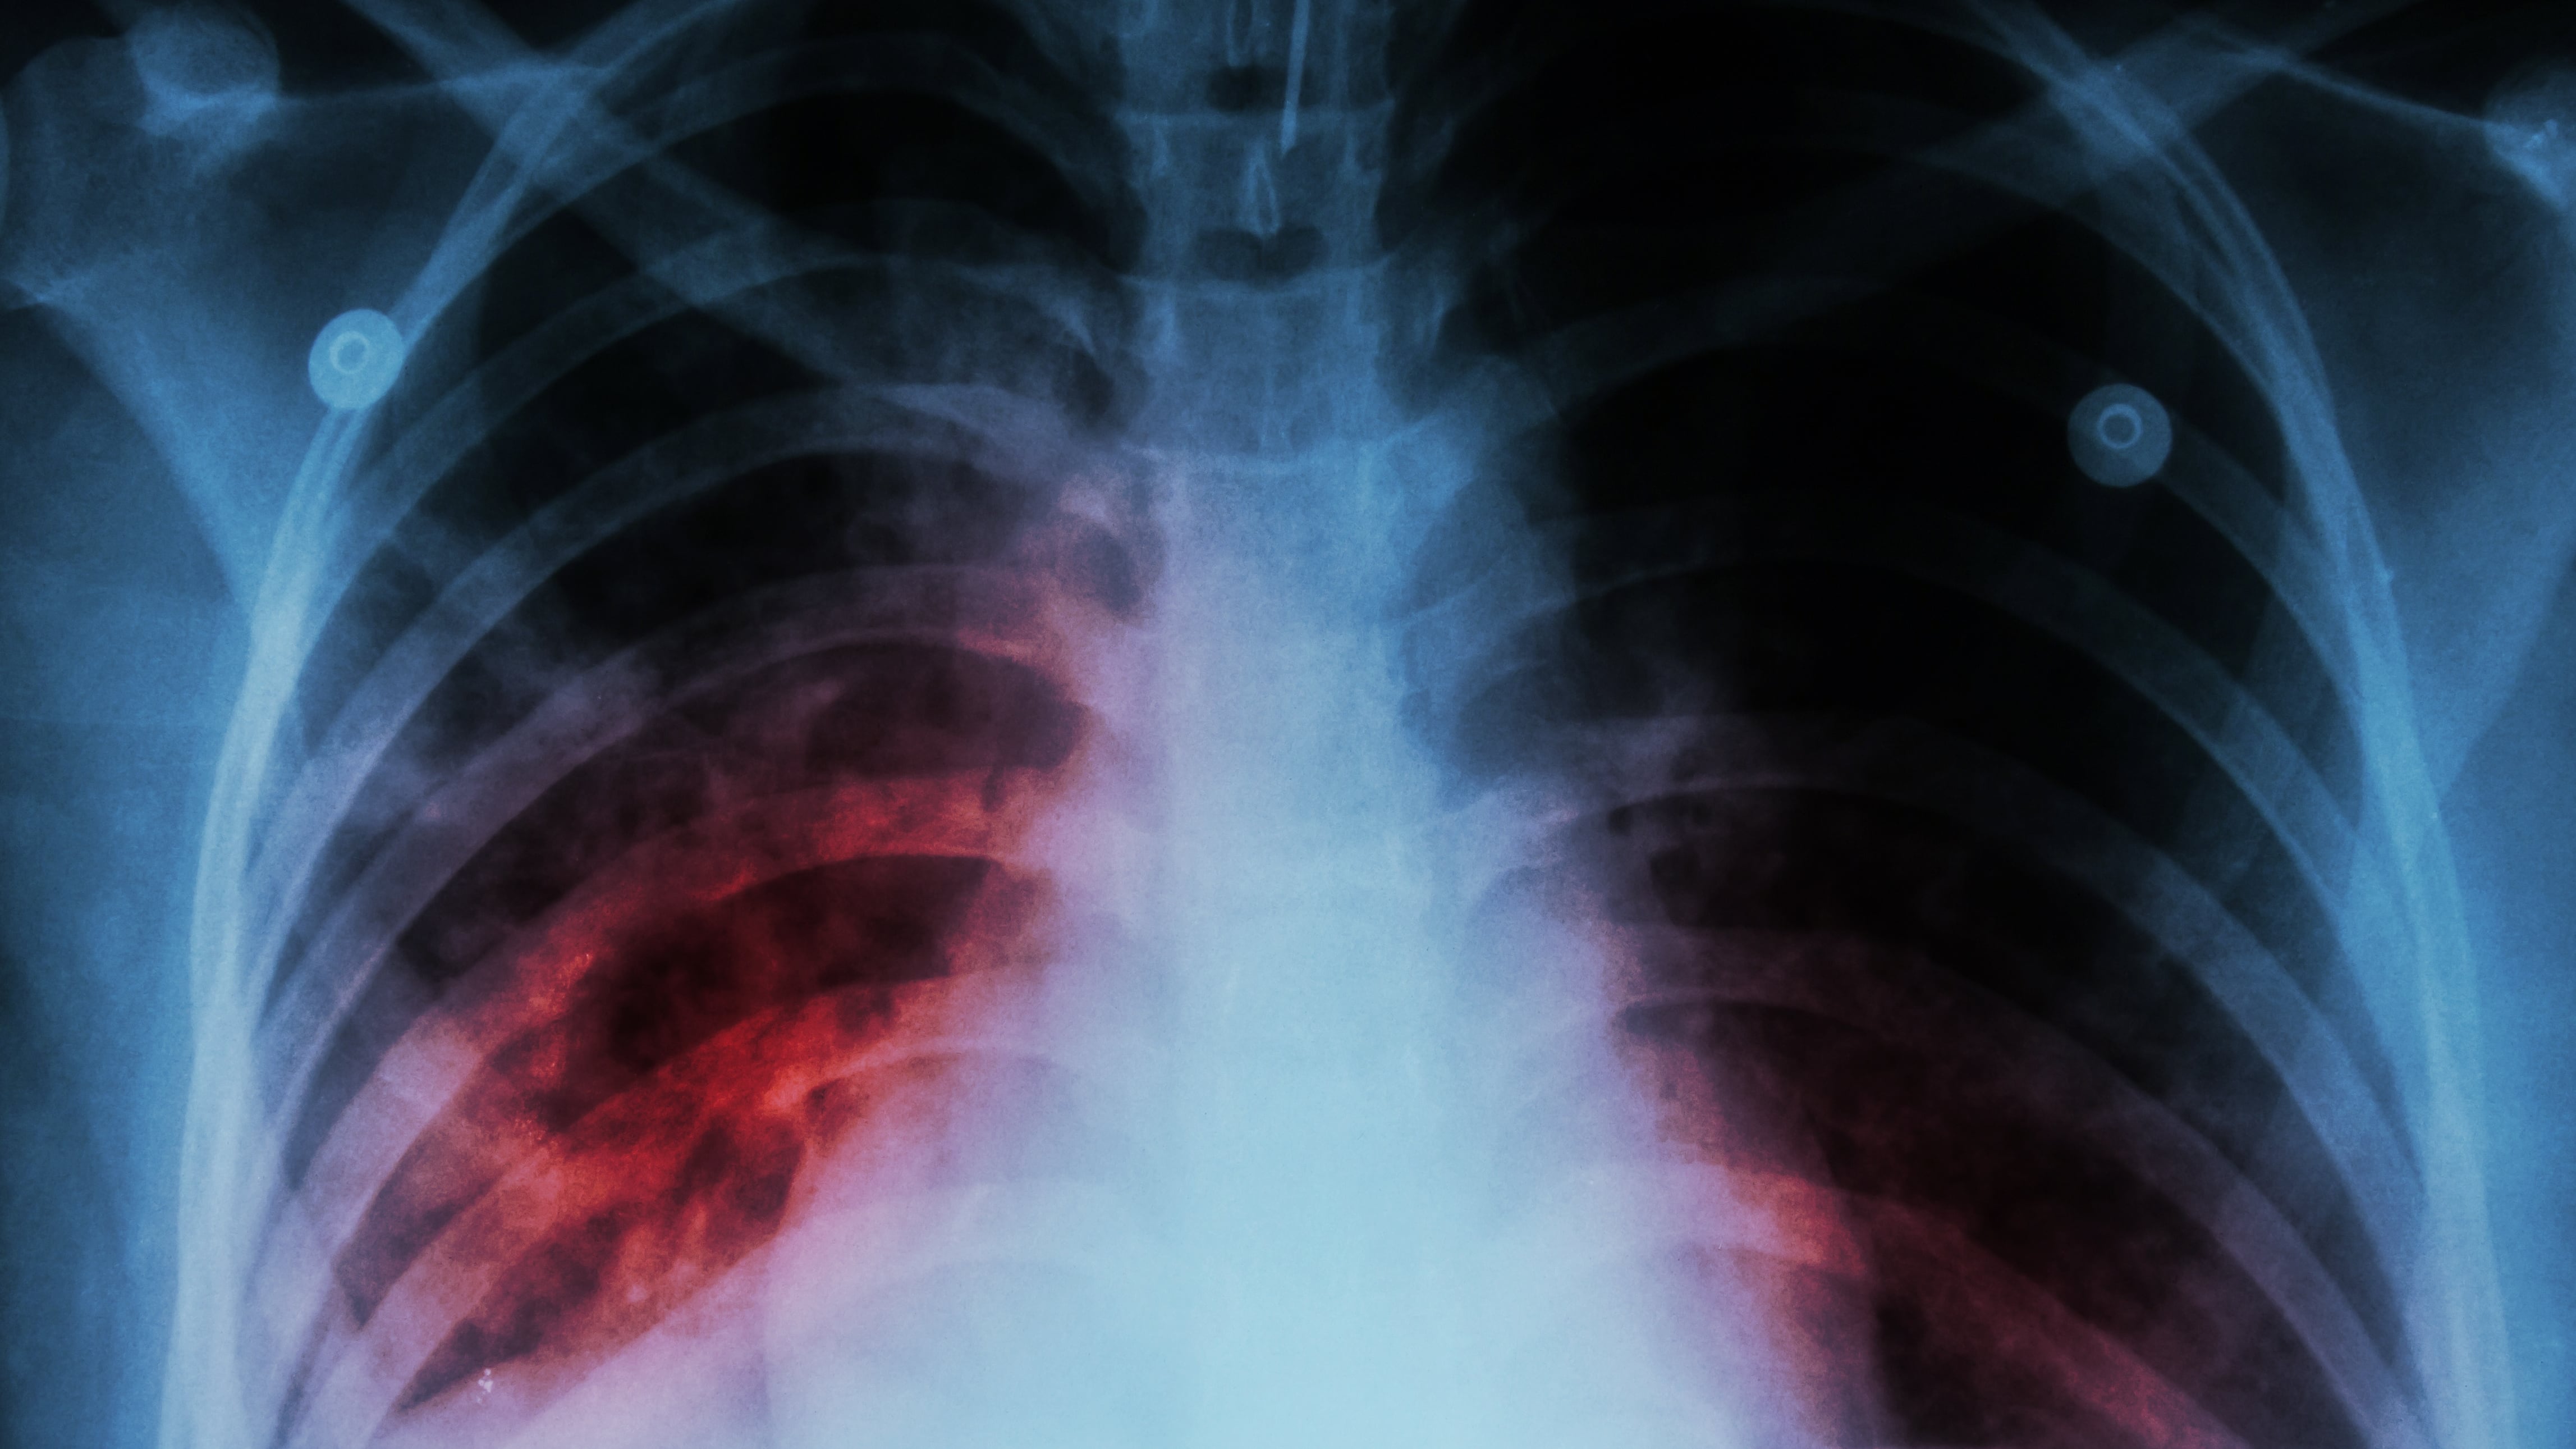

TB is a bacterial disease that primarily affects the lungs, and can spread through the air when a person with active TB disease coughs, sneezes, sings, or talks.